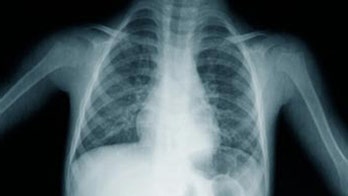

October 27, 2015 X-Ray Lung Cancer Screening Does Not Prevent Deaths A large government study has found that routine chest X-rays, once a common type of screening, do not prevent lung cancer deaths